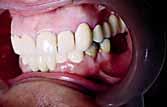

The patient had moderate Class II skeletal pattern with average Frankfort-mandibular planes angle and lower anterior face height. There was no facial asymmetry and the lips were incompetent with the lower lip trapped at rest behind the upper central incisors (Figure 1).

The oral hygiene was fair but needed improvement prior to orthodontic treatment. All teeth from the left permanent second molar to the right have erupted in both the upper and lower arches. The patient had carious lesions in both upper first molars, upper left second molar and lower left first molar. The maxillary arch was spaced with a midline diastema. Furthermore, there was mild lower labial segment crowding (4mm). The incisor relationship was Class II division 1, the overjet was 12 mm whereas the overbite was increased and complete to the palate

and causing trauma to the palatal mucosa. The centrelines were coincident and the buccal segment relationship was 1/2 unit Class II on both sides (Figure 2).